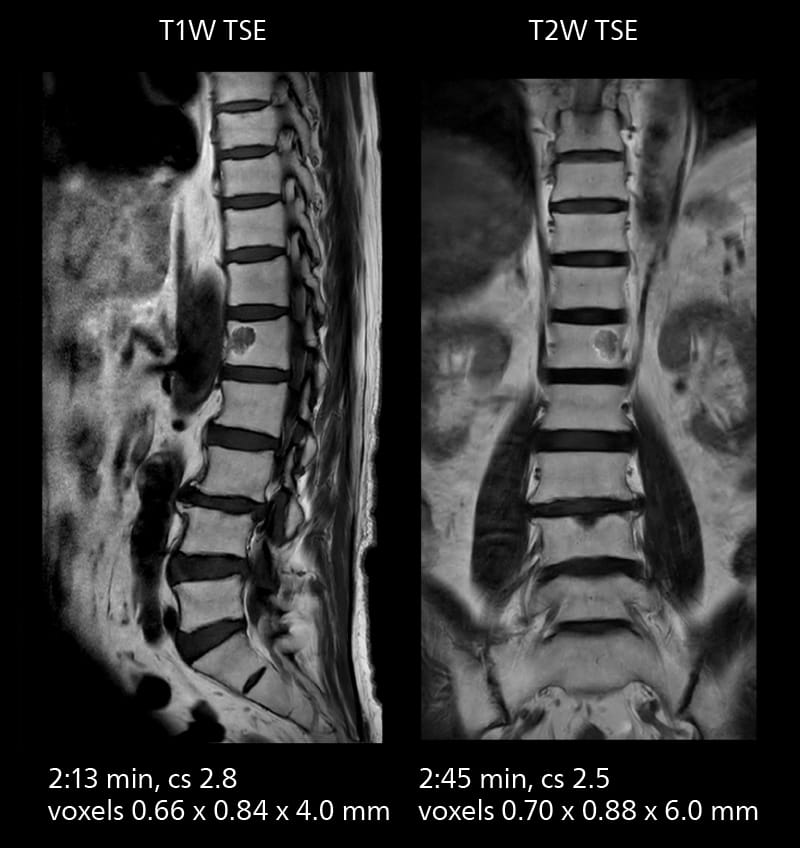

Lumbar spine MRI

Crisp images are obtained with high resolution and short scan times using Elition X. A cyst can be seen.

Lumbar spine MRI

Crisp images are obtained with high resolution and short scan times using Elition X. A cyst can be seen.